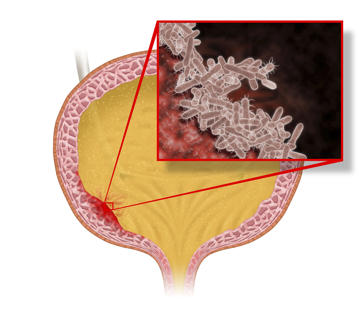

Harnwegsinfektionen (HWI) entstehen durch Bakterienwachstum und Fehlkeimbesiedelung der Blasenschleimhaut. Der medizinische Fachbegriff lautet Zystitis. Wenn die Infektion in die oberen Harnwege (Nieren und/oder Nierenbecken) aufsteigt, spricht man in der Regel von einer Pyelonephritis (Nierenbeckenentzündung).